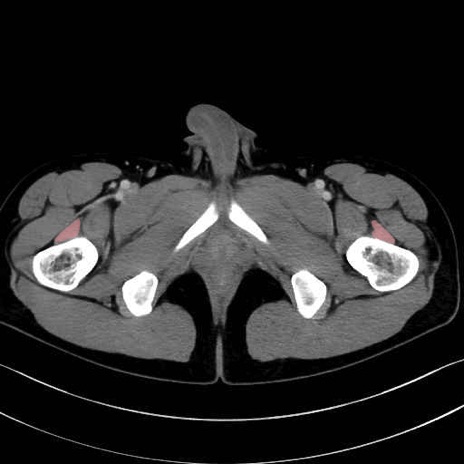

中間広筋 (Vastus intermedius)